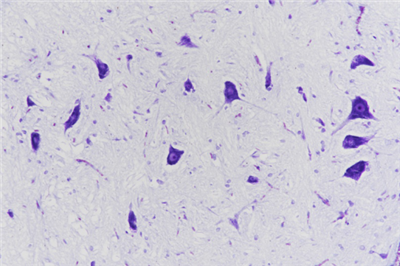

尼氏染色:即Nissl染色法,用來鑒定神經(jīng)元胞體中的尼氏體,是最常用的神經(jīng)細胞染色,在該染色中,尼氏小體清晰可見,可區(qū)分軸突和樹突等。